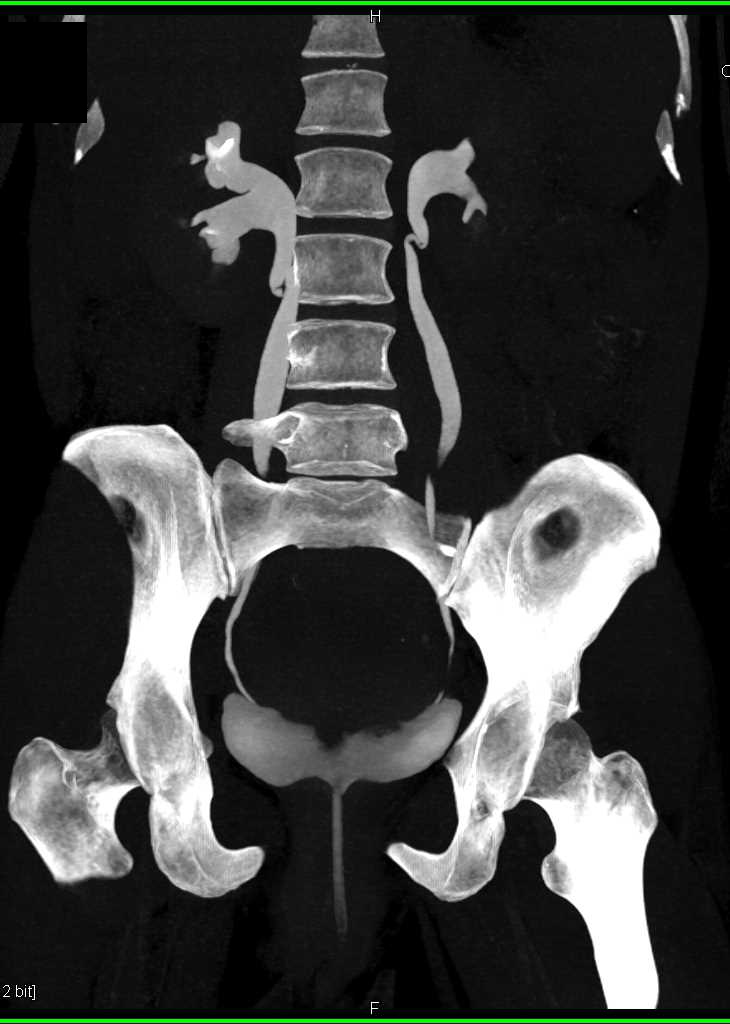

Incidental Bladder Cancer on Lateral Right Wall of Bladder with Enhancement